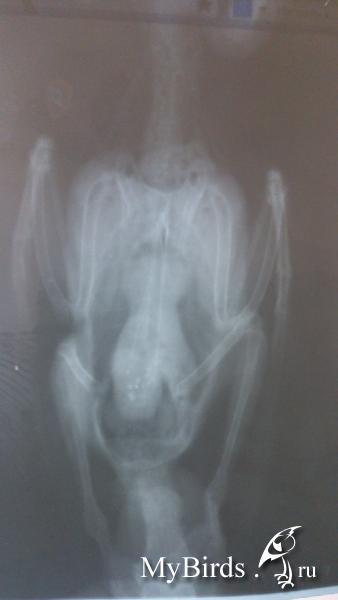

на шприце написано-0,5 мл-50 ед.,мне он сказал набирать3 ед. и разводить водой до 0,3 мл.Прошка поел немного зерносмеси и каши (гречка+пшено+рис)Сейчас помет такой post-58280-1429102056_thumb.jpgpost-58280-1429102086_thumb.jpg Рентген post-58280-1429102182_thumb.jpgpost-58280-1429102240_thumb.jpgpost-58280-1429102287_thumb.jpg

К сожалению, рентген такого качества и с неправильной раскладкой птицы не информативен ВООБЩЕ. По нему нельзя оценить ни размер, ни структуру печени, почек, сердца, легких, пищеварительного тракта.

Смотрите выше еще раз, как надо раскладывать птицу на рентгене.

.Птицу забрали,на рентгене я не присутствовала,рентген я попросила сделать сама,врач согласился только потому-что были свежие растворы,он предупредил,что такой рентген мало информативен,цифрового в Харькове нет ,цель была основная-рассмотреть не расширена-ли железистая часть желудка,у него было подозрение на вирус (не помню как он называется),он недавно с ним столкнулся,у птицы были похожие симптомы,вирус показал анализ крови,сделанный в Голандии,но на снимке,у птицы пораженной вирусом железистая часть была расширена прилично,у нас этого нет..